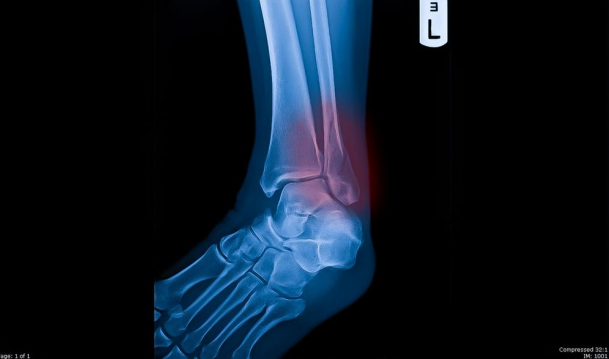

Nitchapa-am stock. (2022). [Image]. Closed fracture left lateral malleolus red highlights is the area where

the bone is broken, black background. https://www.shutterstock.com/image-illustration/closed-fracture-left-lateral-malleolus-red-2049568550